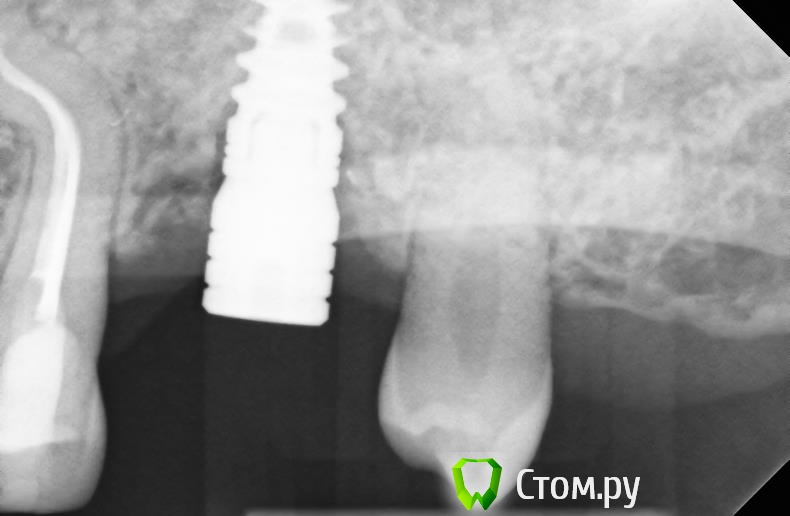

bullbull Опубликовано 20 марта, 2014 Поделиться Опубликовано 20 марта, 2014 Предыстория: мужчина 32 г. Установлен имплант SPI 4,2, 10 в позиции 26. ФДМ через 5-6 месяцев. После фиксации коронки жалобы на постоянные ноющие боли в области имланта, застревание пищи. Мною проведен глубокий кюретаж, назначено лечение. Улучшение на несколько недель. Повторное обращение с теми же жалобами. Локально: некоторая гиперемия десны с вестибулярной стороны, глубина кармана до 3 мм, отделяемого нет. С небной стороны всё в норме.P.S. Нависающий край 25 сточен. У меня появился только после протезирования.Мои мысли: снять коронку, глубокий кюретаж с графтом, возможно, мягкотканная пластика после купирования воспаления, заглушка. А потом всё по новой, через пару месяцев.В общем, нужен совет. Заранее, спасибо. Ссылка на комментарий

АнтонТЛТ Опубликовано 20 марта, 2014 Поделиться Опубликовано 20 марта, 2014 Ремоделировка кости на том уровне на котором должна быть, но из-за слишком глубокой установки имплантата появился глубокий карман. Графт не поможет. Я бы выкрутил и переставил на нужную глубину. 1 Ссылка на комментарий

r3yand Опубликовано 20 марта, 2014 Поделиться Опубликовано 20 марта, 2014 А что за дизайн абатмента?Он сам создает нависающий край, там и происходит скопление пищи имхо. Какой-то обратный платформ-свитч получился... Ссылка на комментарий

kriokov Опубликовано 20 марта, 2014 Поделиться Опубликовано 20 марта, 2014 А что за дизайн абатмента?Он сам создает нависающий край, там и происходит скопление пищи имхо. Какой-то обратный платформ-свитч получился...тоже не торопился бы имплантат удалятьчто настораживает- видимые дефекты в посадке коронки на абатменте- какойто "мутняк" по переферии от абатмента, может цемента остатки?Снял бы с ортопедом конструкцию, ревизию этой зоны сделал бы, если цемент и грануляции до платформы, то удалил бы их, и фдм на месяц. 3 Ссылка на комментарий

carloss Опубликовано 20 марта, 2014 Поделиться Опубликовано 20 марта, 2014 а что тут думать - недосела коронка.. лечение - только терапия с ортопедией 2 Ссылка на комментарий

j-kost9 Опубликовано 20 марта, 2014 Поделиться Опубликовано 20 марта, 2014 Мои мысли,что коронка не села,+цемент,глубокая установка сыграло сыграло свою роль,т.к вы запрограммировали глубокую биологическую ширину,тем самым создались условия для инфекции.Если бы это был ан..лоз например думаю такой ремоделировки не было бы,опять же если это не цемент. Ссылка на комментарий